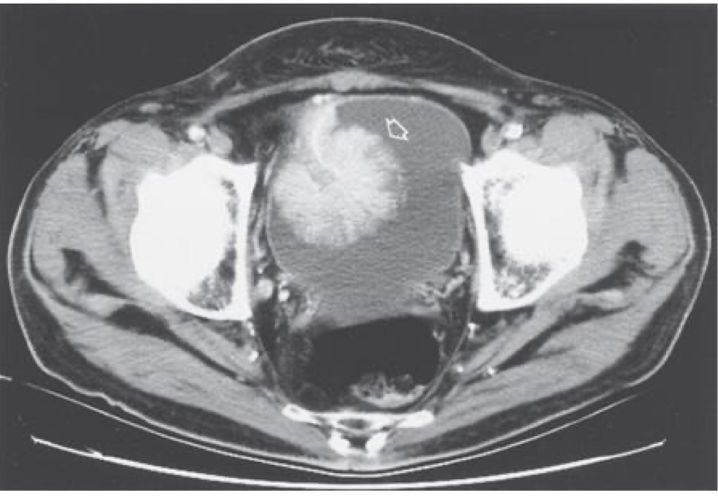

What is this and what type of scan

Polycystic kidney disease, CT scan